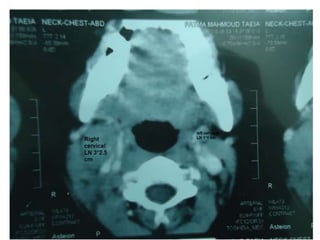

• CT neck : Multiple bilateral upper and lower deep cervical LNs the largest one on RT side

about 3*2.5 cm, the largest one on the left side about 1 *1 cm.